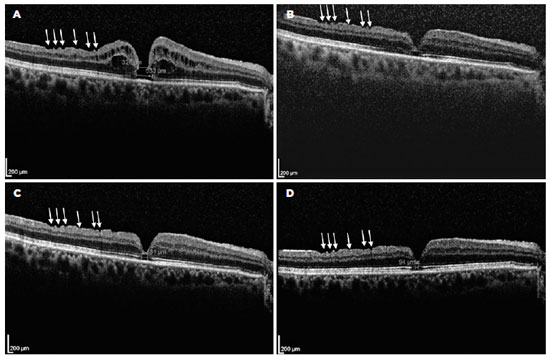

A 68-year-old man who had undergone combined cataract and iFTMH surgery in his right eye (OD) 15 months before at another institution presented at our outpatient clinic for routine examination. The best-corrected visual acuity (BCVA) in OD was counting fingers, with pseudophakia and normal intraocular pressure. Fundus examination evidenced an iFTMH in the right eye; the left eye showed no abnormal findings. The patient’s presurgical spectral domain optical coherence tomography (SD-OCT) study demonstrated a FTMH, but the iFTMH was not measured (Figure 1). A new SD-OCT scan revealed the persistence of the iFTMH, with 326 and 533 microns of mid- and base-hole diameters, respectively (Figure 2A). A new surgery was offered, but the patient declined. Thus, he was set for follow-up every 6 months.